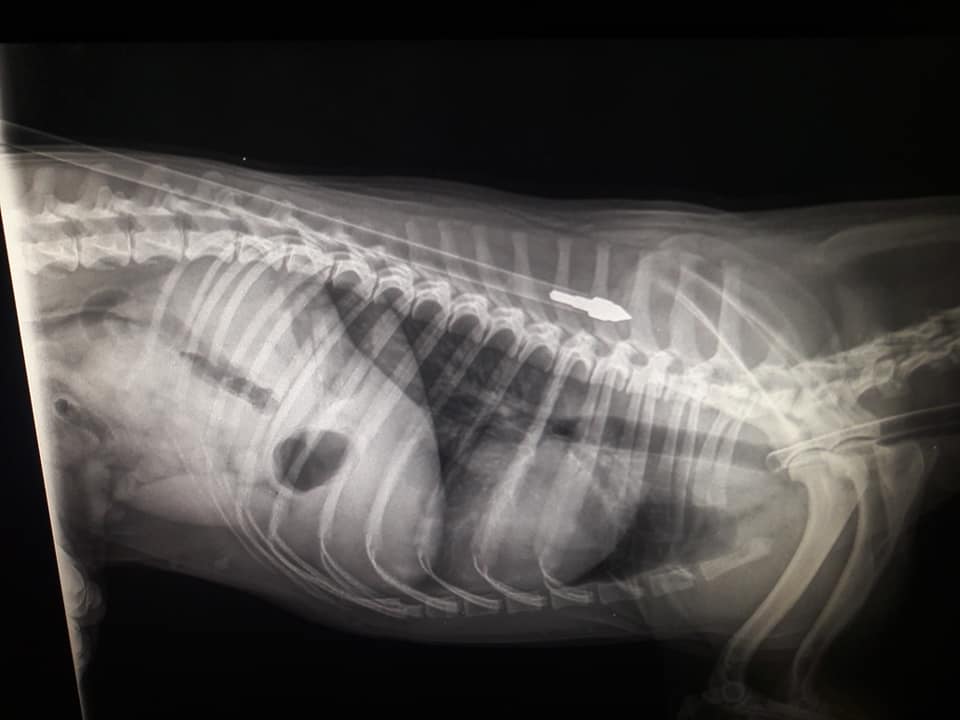

“Un cane è stato gravemente ferito a Scicli (Ragusa) con un balestra da caccia. A trovare l’animale agonizzante la padrona che lo ha subito portato dal veterinario. È stato necessario un intervento chirurgico per rimuovere la freccia conficcata nella parte superiore della schiena. Appena qualche millimetro più in là e per il povero animale, divenuto bersaglio vivente di qualche folle criminale, non ci sarebbe stato scampo alla morte”, lo afferma in una nota Rinaldo Sidoli, portavoce di Alleanza Popolare Ecologista (Ape). “L’ennesimo episodio di crudeltà – aggiunge – nei confronti di creature indifese. Proprio due mesi fa un randagio è stato trovato morto in questa località, ucciso con un grosso sasso. Chiediamo al sindaco Vincenzo Giannone di condannare il gravissimo episodio avvenuto nel suo comune, e di costituirsi parte civile nei procedimenti giudiziari che saranno avviati in caso di individuazione dei responsabili. Servono iniziative, anche legislative, immediate e risolutive. Ogni giorno vengono uccisi decine e decine di animali nella maniera più atroce. L’animalicidio rimane impunito a causa dei buchi legislativi presenti nel sistema giuridico italiano. È arrivato il momento che il legislatore aggiorni la normativa. L’art. 544 bis prevede una pena di massimo 2 anni di reclusione: tra riti abbreviati, sospensione della pena e messa alla prova, praticamente chi si macchia di simili crimini non va in carcere”. “Sollecitiamo – conclude Sidoli – il Ministro della Giustizia, Alfonso Bonafede e al Ministro dell’Ambiente, Sergio Costa, a tenere fede agli impegni assunti di fronte a milioni di cittadini. La politica e le istituzioni devono passare dalle parole alle iniziative concrete. Si può e si deve ripartire riprendendo il DDL S. 1078 a firma del senatore Gianluca Perilli (M5s), oppure sbloccando il PDL n. 847 dell’on. Patrizia Prestipino (Pd)”.